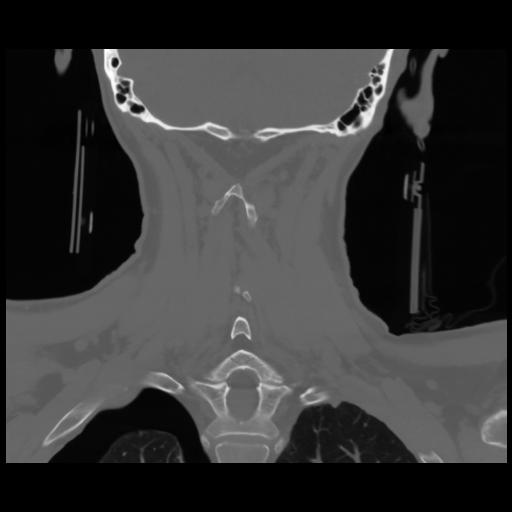

13 P.BLANDAS,,Coronal,2.000,P.BLANDAS,Coronal,